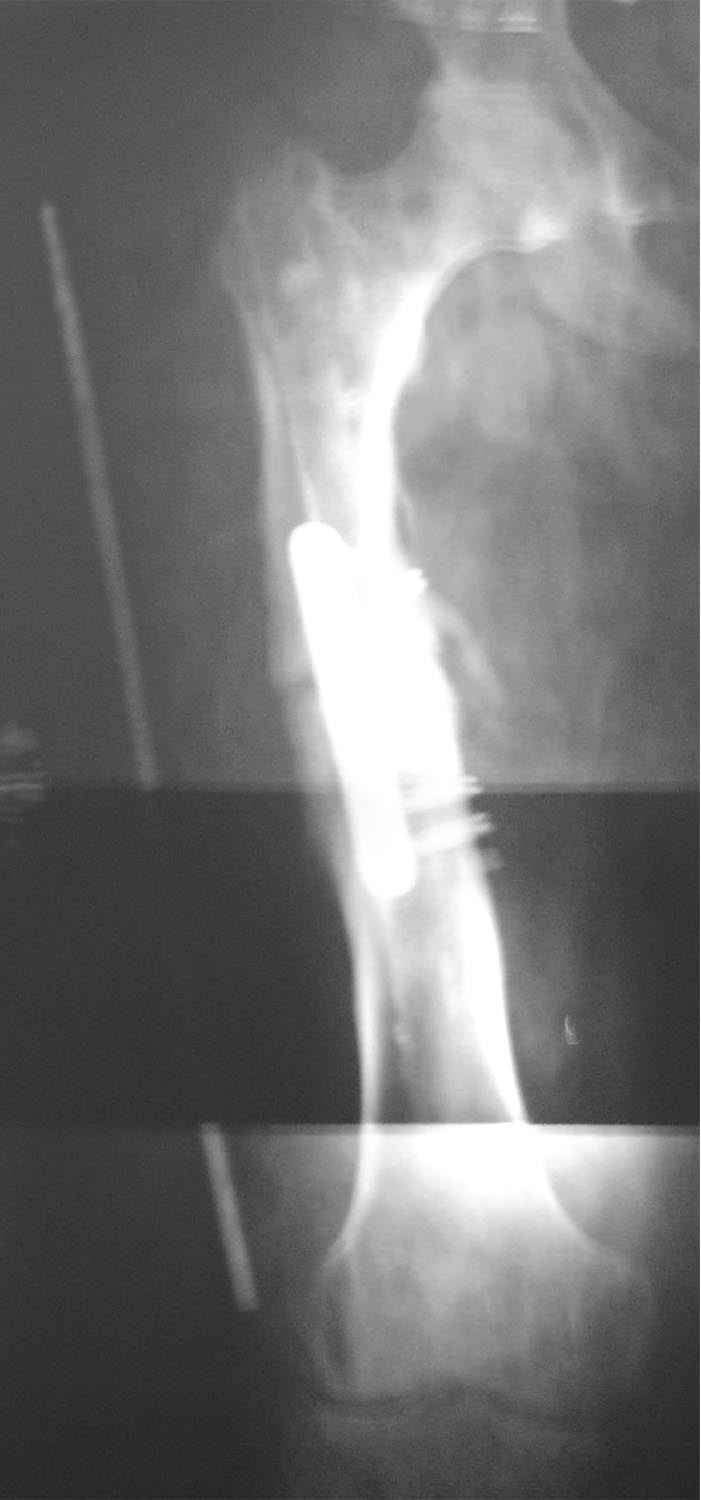

Re: ложный сустав средней трети бедра

укорочение 15мм, клинически варуса нет. в приложении снимок на 2 пленках с центр на суставах, с приклеенной на уровне кости стержнем L-300mm,d-5mm.